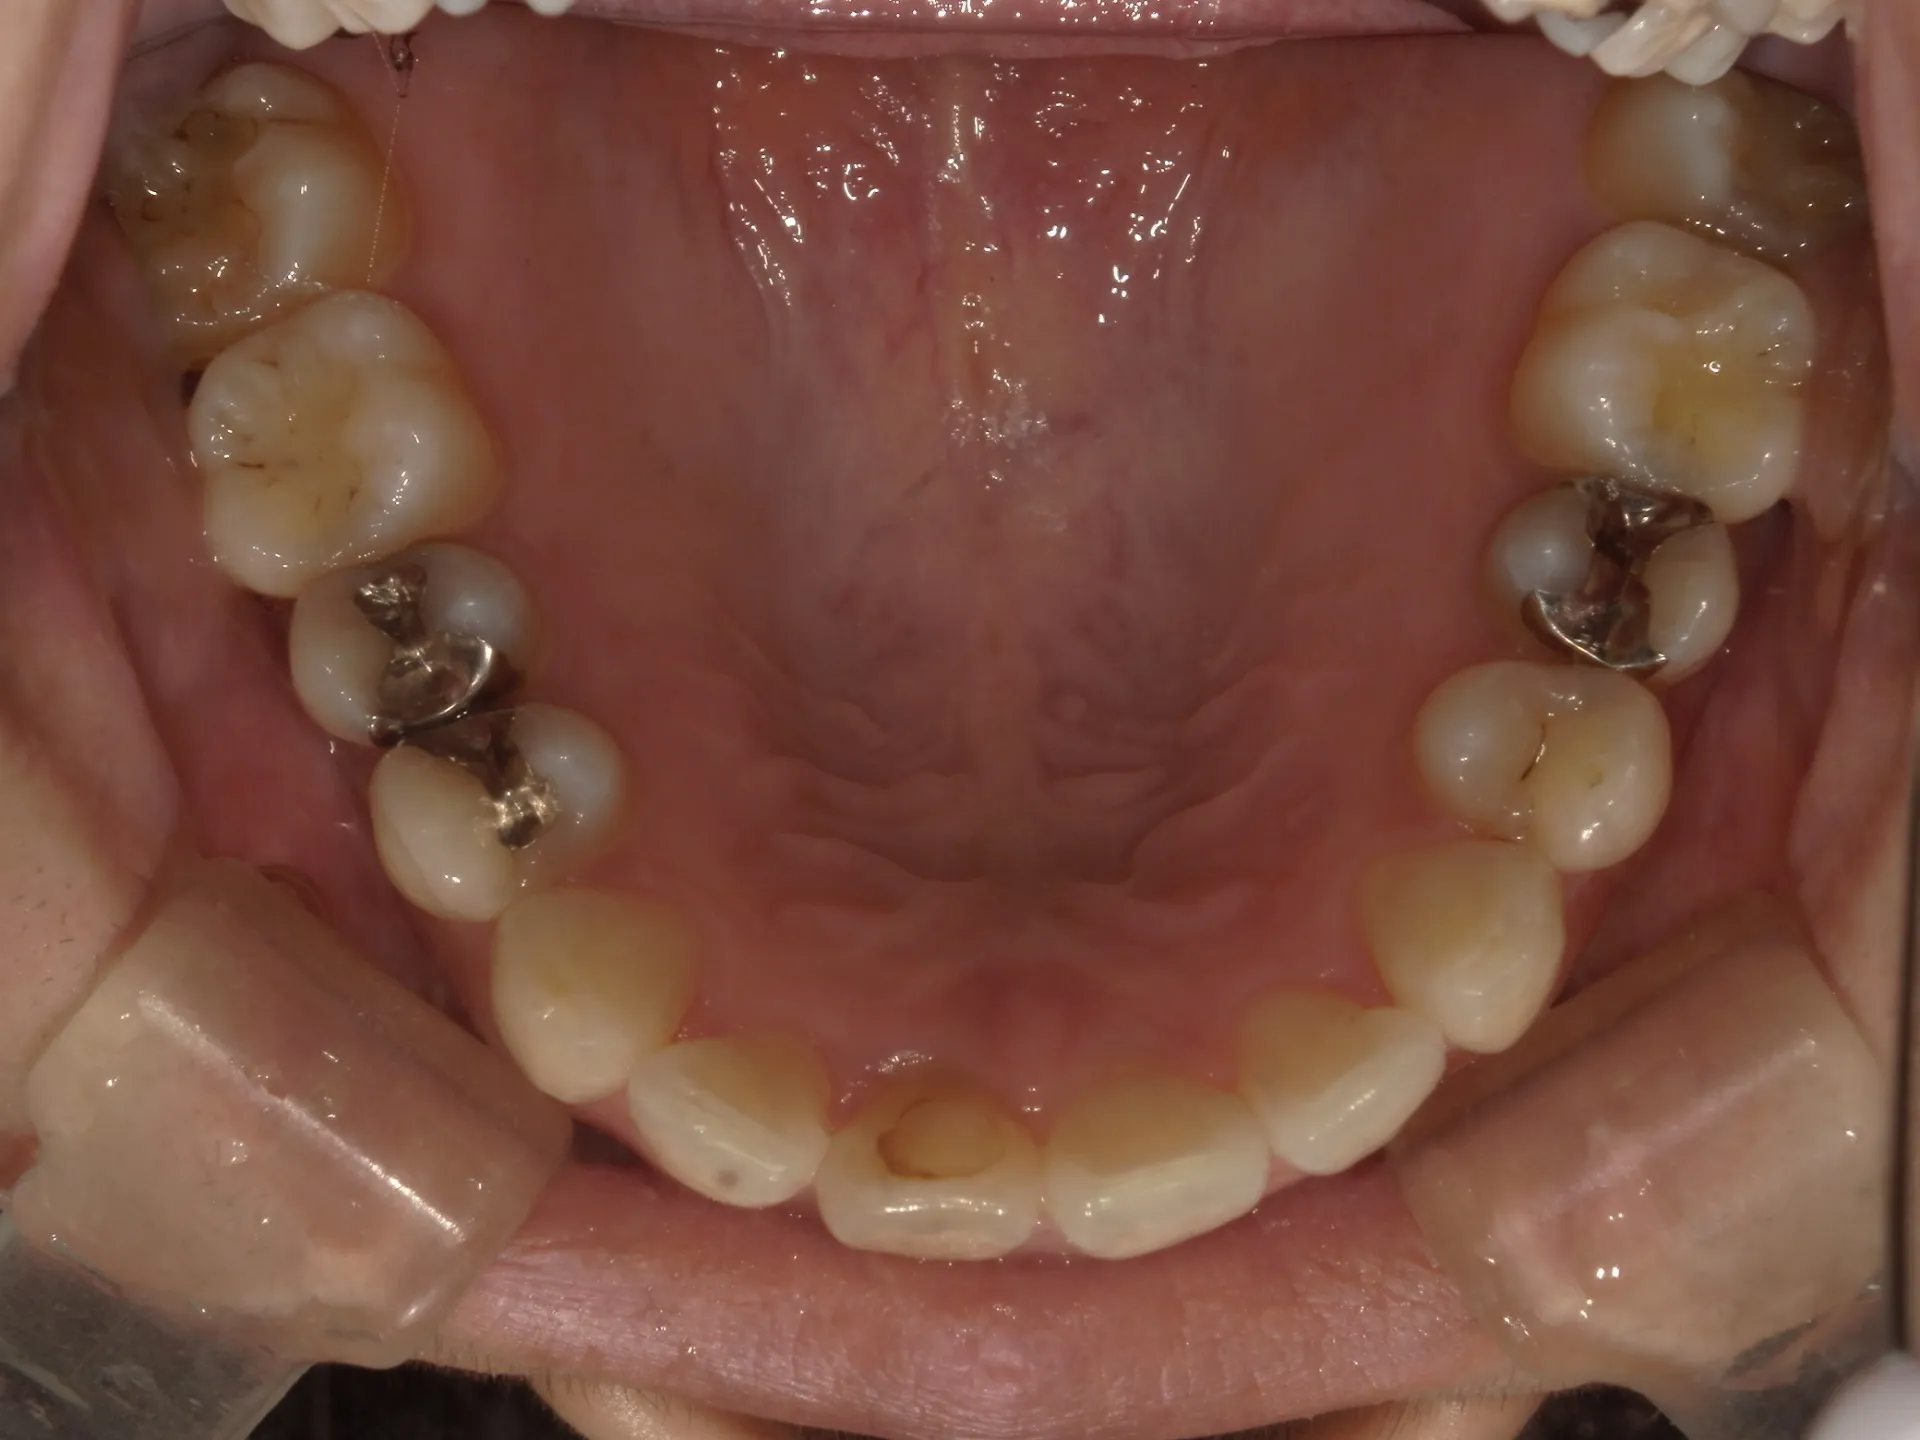

今回はねじれてしまった前歯の矯正治療をインビザラインというマウスピース矯正で治療した症例をご紹介いたします。